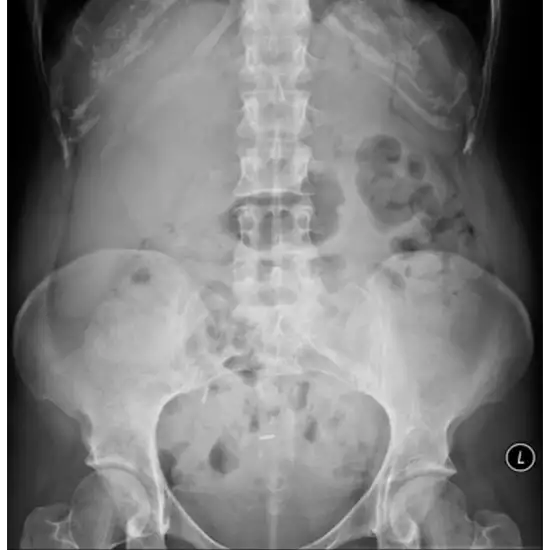

A kidney, ureter, and bladder X-ray, often known as a KUB X-ray, is helpful in seeing the organs that make up the urinary and digestive systems. It is carried out to ascertain whether or not there is a blockage in the intestinal tract, foreign items in the stomach, tumors, gallstones, or kidney stones. In addition to this, it can reveal information about the size, shape, and location of the kidneys, ureters, and bladder.